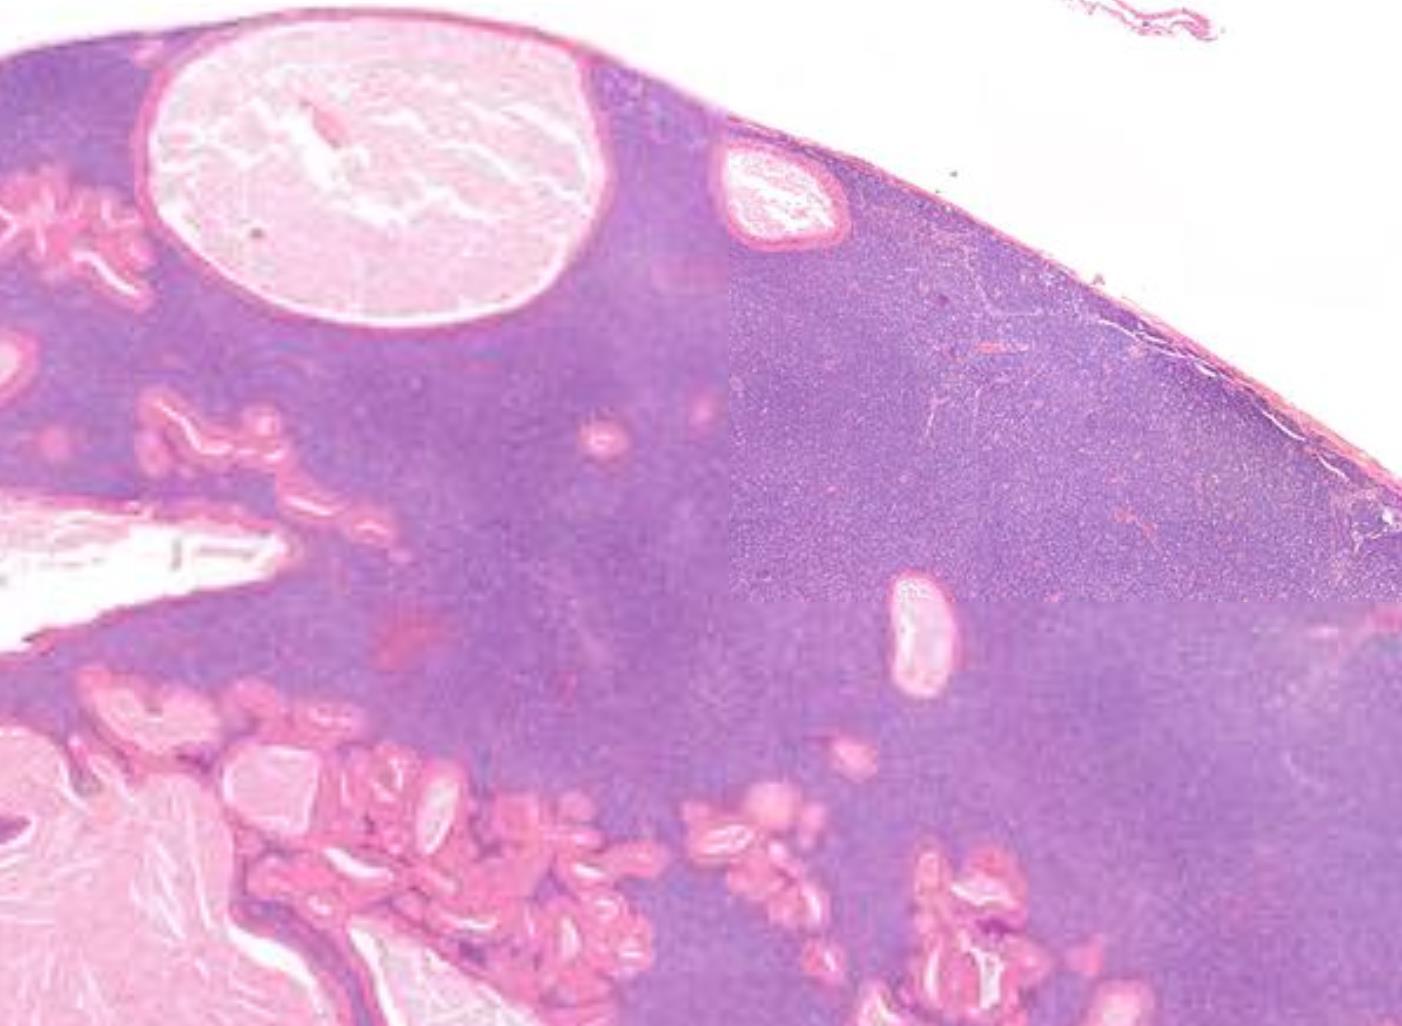

Case 17 71-year-old, Female Large Cystic Lesion Posterior Mandible.

??

Case 17 Diagnosis Ameloblastoma